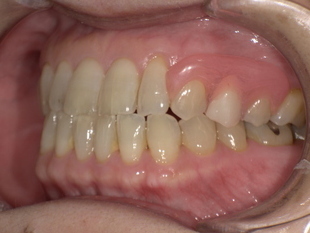

■ 【Before→After】ノンクラスプ義歯で口元の印象が大きく若返り

▼ 治療後(ノンクラスプデンチャー装着)

-

歯ぐきの色に馴染む樹脂で金具ゼロの自然な見た目

厚みが薄く、軽いため痛みほぼゼロの快適さ

義歯のフィット感が高く、噛む力も安定

口元がふっくらし、見た目・印象が10歳以上若返る